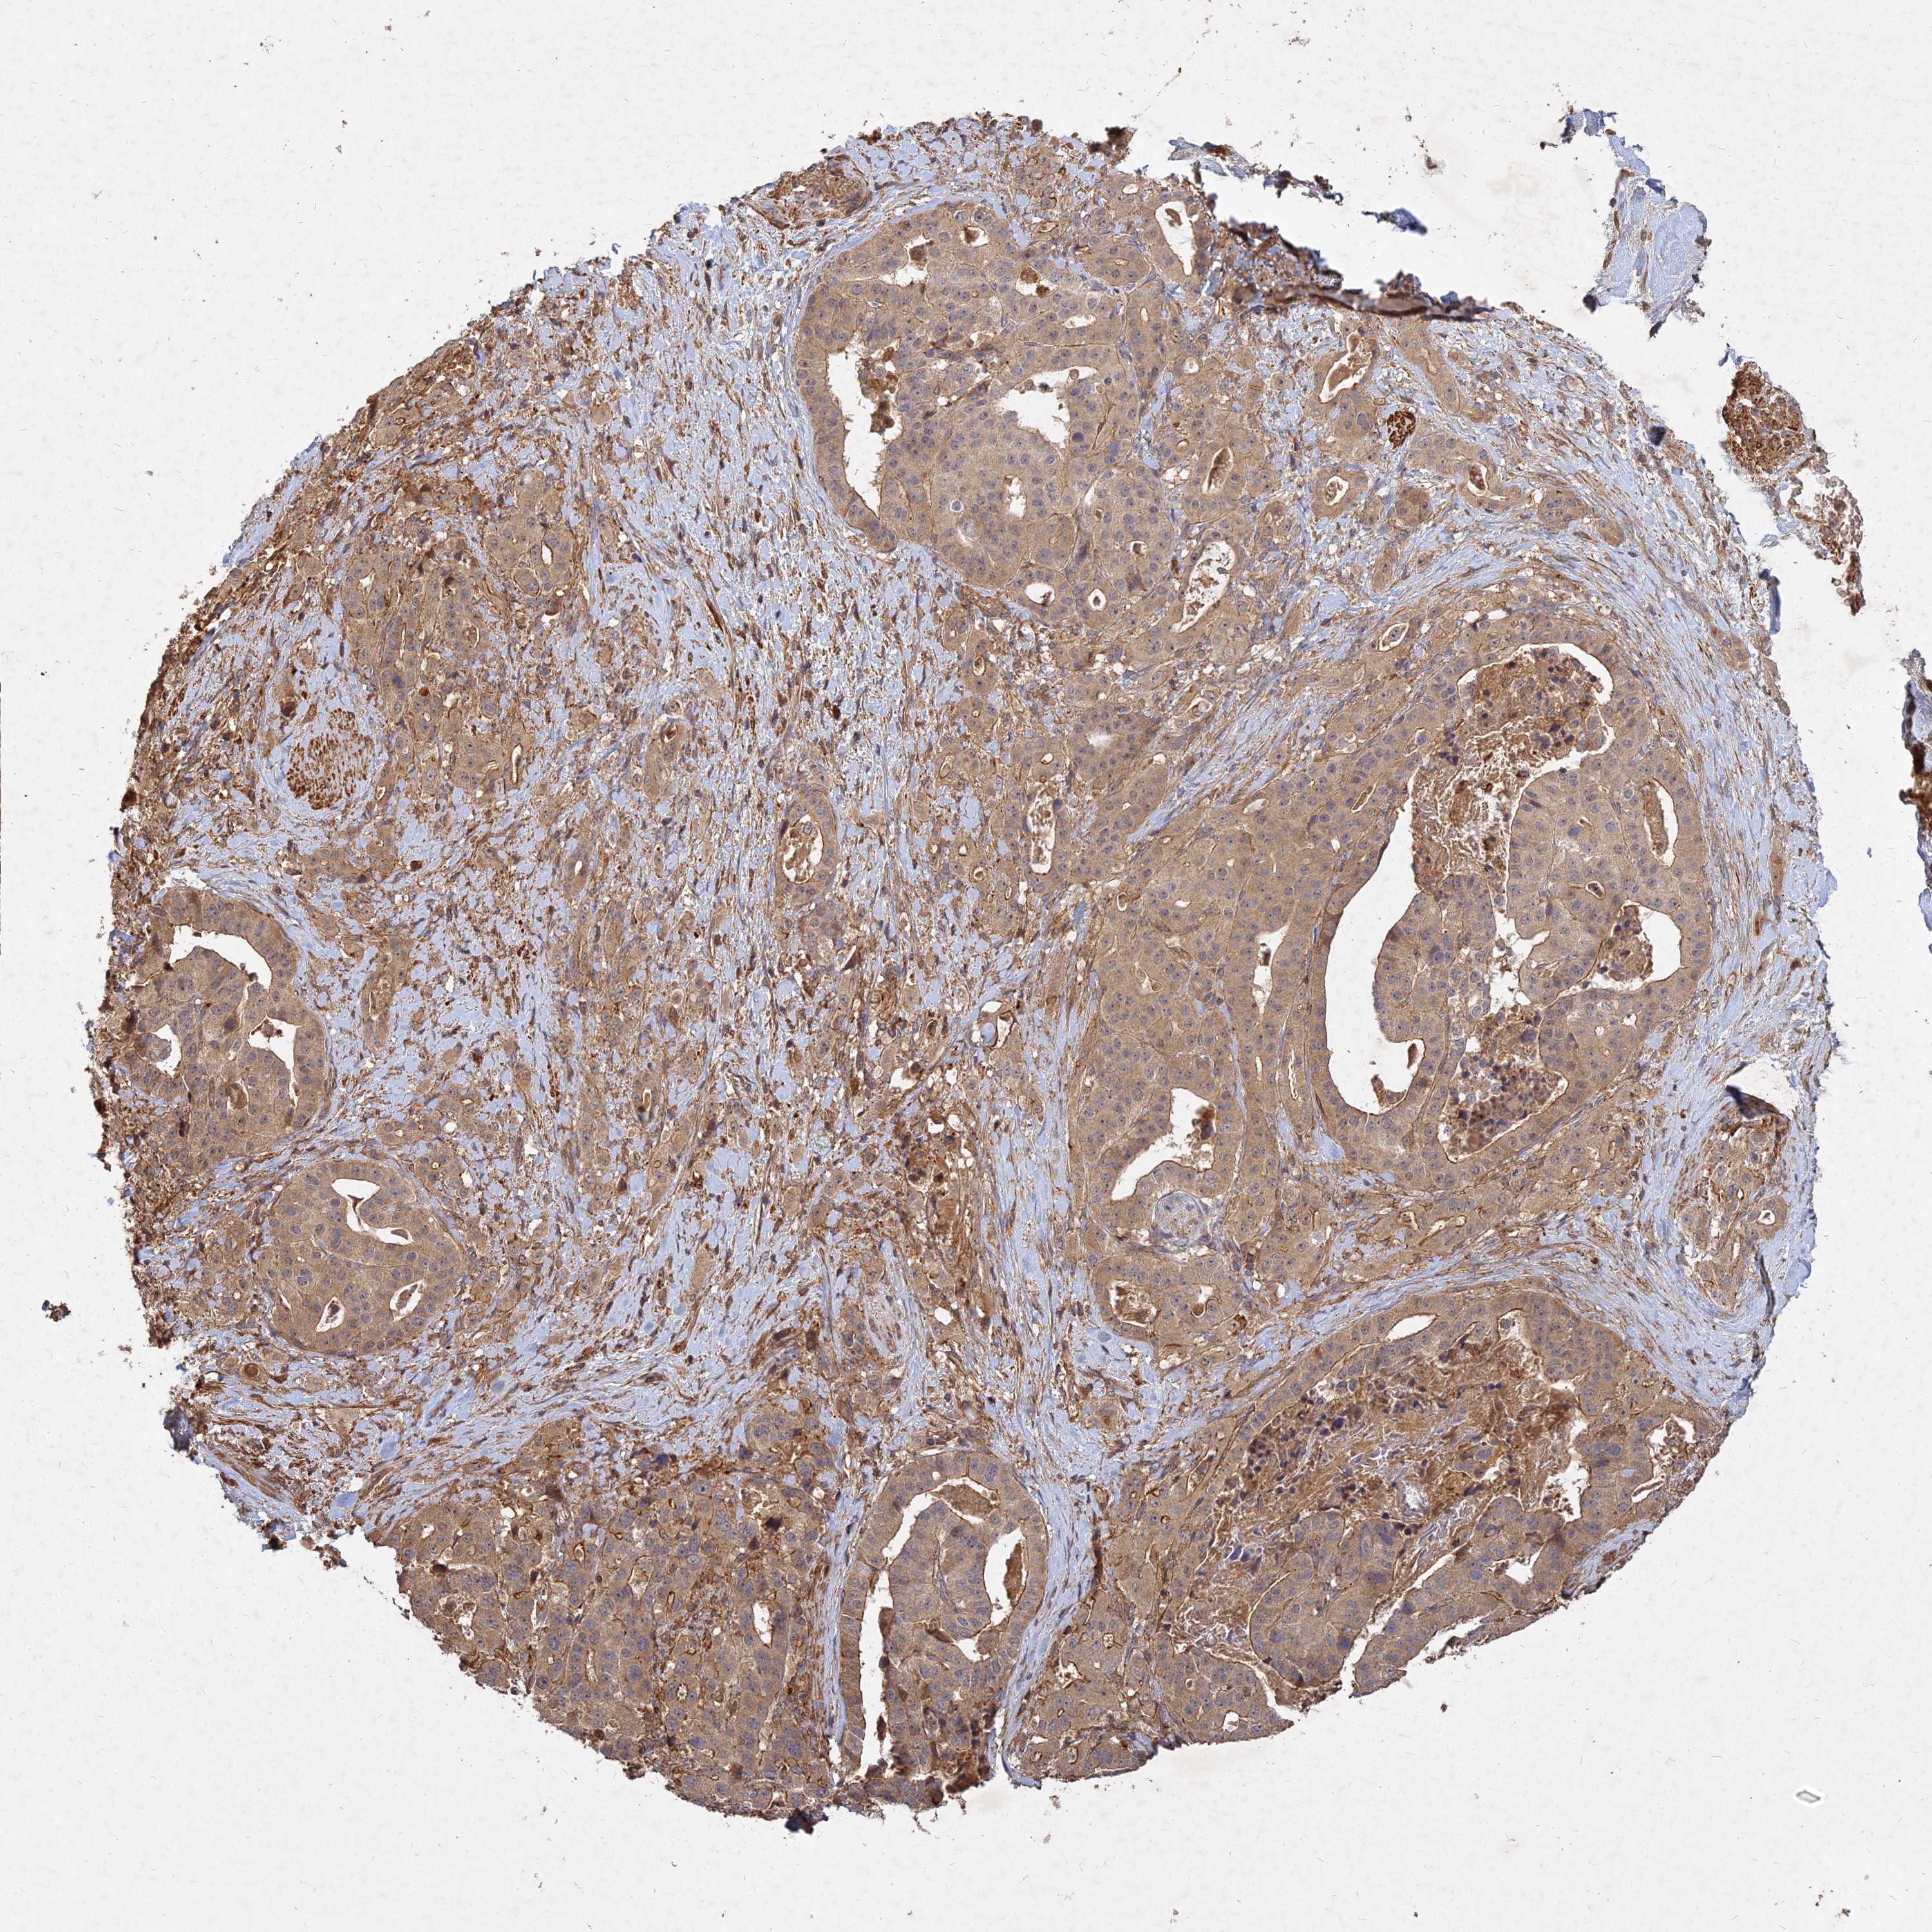

STOMACH CANCER - Protein expressioni

A mouse-over function shows sample information and annotation data. Click on an image to view it in a full screen mode. Samples can be filtered based on level of antibody staining by selecting one or several of the following categories: high, medium, low and not detected. The assay and annotation is described here.

Note that samples used for immunohistochemistry by the Human Protein Atlas do not correspond to samples in the TCGA dataset.

Antibody stainingi

Antibody staining in the annotated cell types in the current human tissue is reported as not detected, low, medium, or high, based on conventional immunohistochemistry profiling in selected tissues. This score is based on the combination of the staining intensity and fraction of stained cells.

Each image is clickable and will lead to virtual microscopy that enables deeper exploration of all samples and also displays staining intensity scores, fraction scores and subcellular localization as well as patient and tissue information for each sample.

Antibody HPA045161

Staining

High

Medium

Low

Not detected

Intensity

Strong

Moderate

Weak

Negative

Quantity

>75%

75%-25%

<25%

None

Location

Nuclear

Cytoplasmic/membranous

Cytoplasmic/membranous,nuclear

Adenocarcinoma, NOS